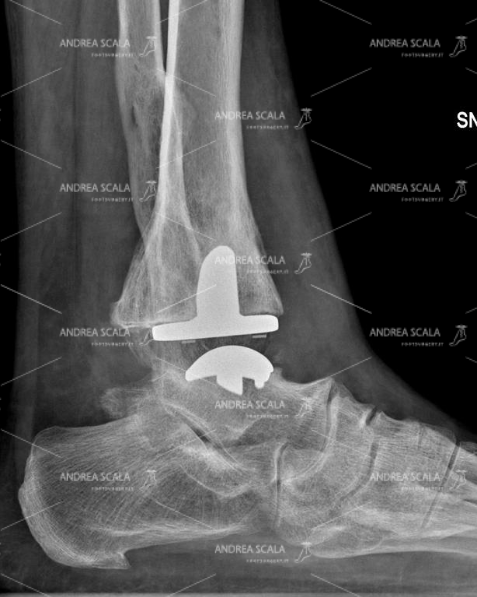

La RXgrafia eseguita nelle stesse condizioni mostra l’impianto della protesi di caviglia. In questo caso particolare è stata scelta una protesi con il fittone tibiale che è stato allineato secondo L’ASSE BIOMECCANICO allo scopo di assicurare alla protesi un funzionamento migliore e una vita più lunga.

La RXgrafia laterale dopo l’impianto della protesi mostra che l’articolazione della caviglia è stata ricostruita. E’presente lo spazio articolare. In questo caso particolare è stata scelta una protesi con il fittone tibiale.